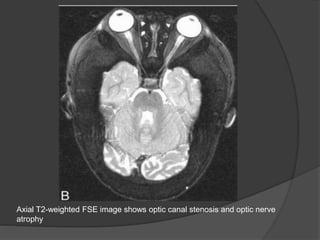

Severe bilateral optic canal narrowing (arrows) in a 4-yr-old patient with complete

loss of vision in the left eye and 20/80 visual acuity in the right eye.

Axial T2-weighted FSE image shows optic canal stenosis and optic nerve

atrophy

Severe bilateral opticcanal narrowing (arrows) in a 4-yr-old patient with complete loss of vision in the left eye and 20/80 visual acuity in the right eye.

Axial T2-weighted FSEimage shows optic canal stenosis and optic nerve atrophy